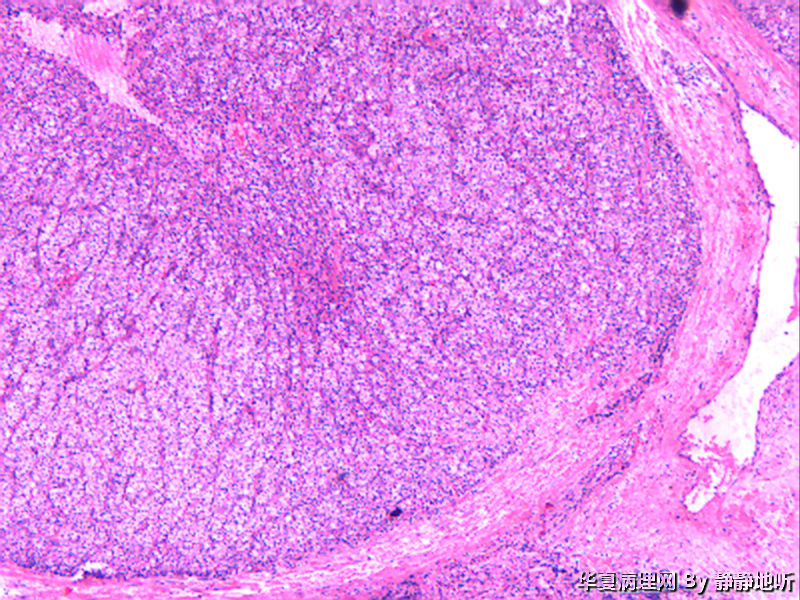

骶韧带肿物

• 骶韧带肿物图1

女性 52岁,盆腔骶韧带肿物。肿瘤球形,直径约2.5厘米,表面光滑,切面结节状,灰粉色。镜下见大量上皮细胞巢,间质为平滑肌。免疫组化:Vimentin +   SMA梭形细胞+  EMA-   CD10-

上级医院做免疫组化:CK+ EMA+  Vimentin +  s-100 弱+  p63-   SMA血管+    CD34 血管+  HMB-45 +  Melanoma+   desmin +   ki-67约20%

会诊意见:低度恶性PEComa